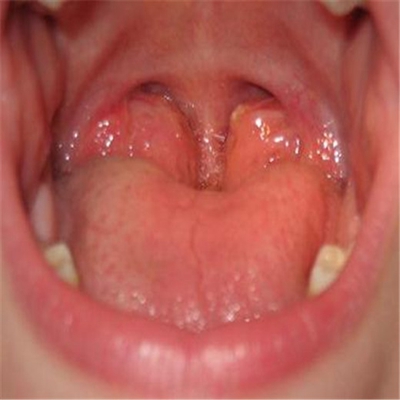

扁桃體惡性腫瘤圖片

扁桃體癌圖 (8)